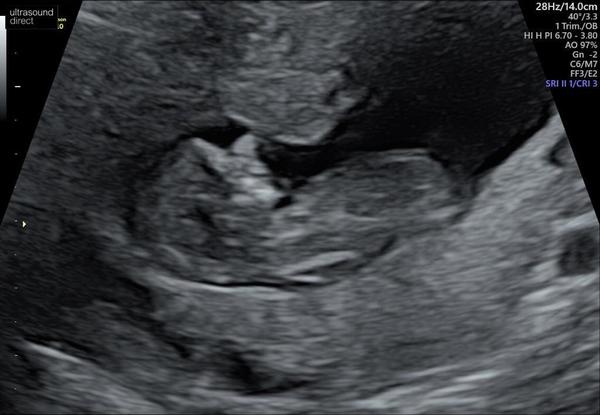

Just got home from my scan, all good! I’m 10+1 today and baby was measuring 10+0, wriggling around like crazy kicking its teeny arms and legs. Feeling excited and happy and also quite overwhelmed!

@DinoGreen what a lovely picture!! X

Congrats @DinoGreen very clear!